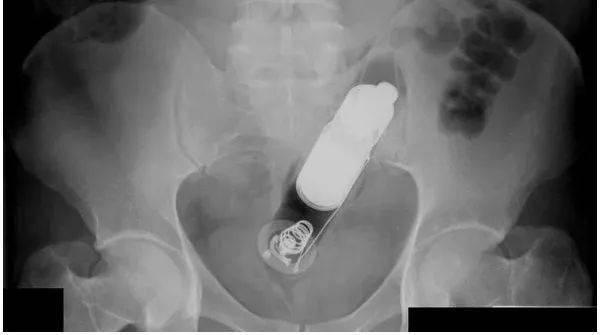

辛集市的奇葩男子"下体塞异物"殊不知竟是一根木棍子